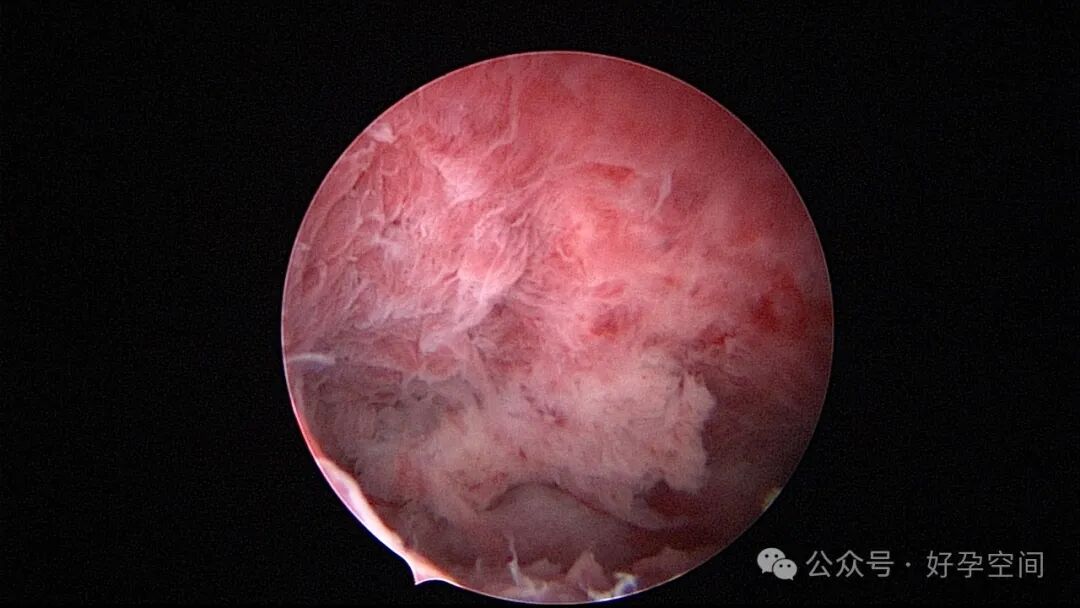

病例1:32岁,G8P3,剖宫产3次,本次停经50+天,计划外妊娠,宫腔镜辅助下清宫,见剖宫产瘢痕憩室,宫腔后壁2.5cm*2.0cm组织难以清除,宫腔镜电切送病检,病检结果为宫腔妊娠组织。

病例2:32岁,G3P1,剖宫产1次,本次停经60+天,稽留流产,宫腔镜辅助下清宫,宫腔广泛粘连,单极电针分粘。术后19天宫腔镜二探,宫腔后壁见1.0cm*1.0cm组织凸起,宫腔镜电切送病检,病检结果为宫腔增殖期样子宫内膜,另见血凝块及纤维素样坏死组织,浅肌层内可见少许滋养叶细胞(病理医生曾与临床医生沟通,病理图片跟超常胎盘部位反应很相似,但最后仅给出了以上病检诊断)。

病例3:26岁,孕产史不详,本次停经60+天,稽留流产,宫腔镜辅助下清宫,见剖宫产瘢痕憩室,左侧宫角2.0cm*1.5cm组织凸起,难以清除,宫腔镜电切送病检,病检结果为蜕膜组织及平滑肌组织。

病例4:34岁,G3P1,顺产1次,本次停经40+天,计划外妊娠,宫腔镜辅助下清宫,宫腔前壁2.cm*1.0cm组织难以清除,家属拒绝切除送病检,术后2周复查B超,宫腔查见1.1cm*1.0cm占位,无血流信号,门诊随访。

从以上病例可知,人流不全、药流不全有时候难以避免,宫内占位也并非都是胚物残留,门诊手术医生可能成为背锅侠。宫腔镜辅助下清宫可以最大限度地避免残留,及时发现宫腔内占位病变,切除送病检以明确诊断。